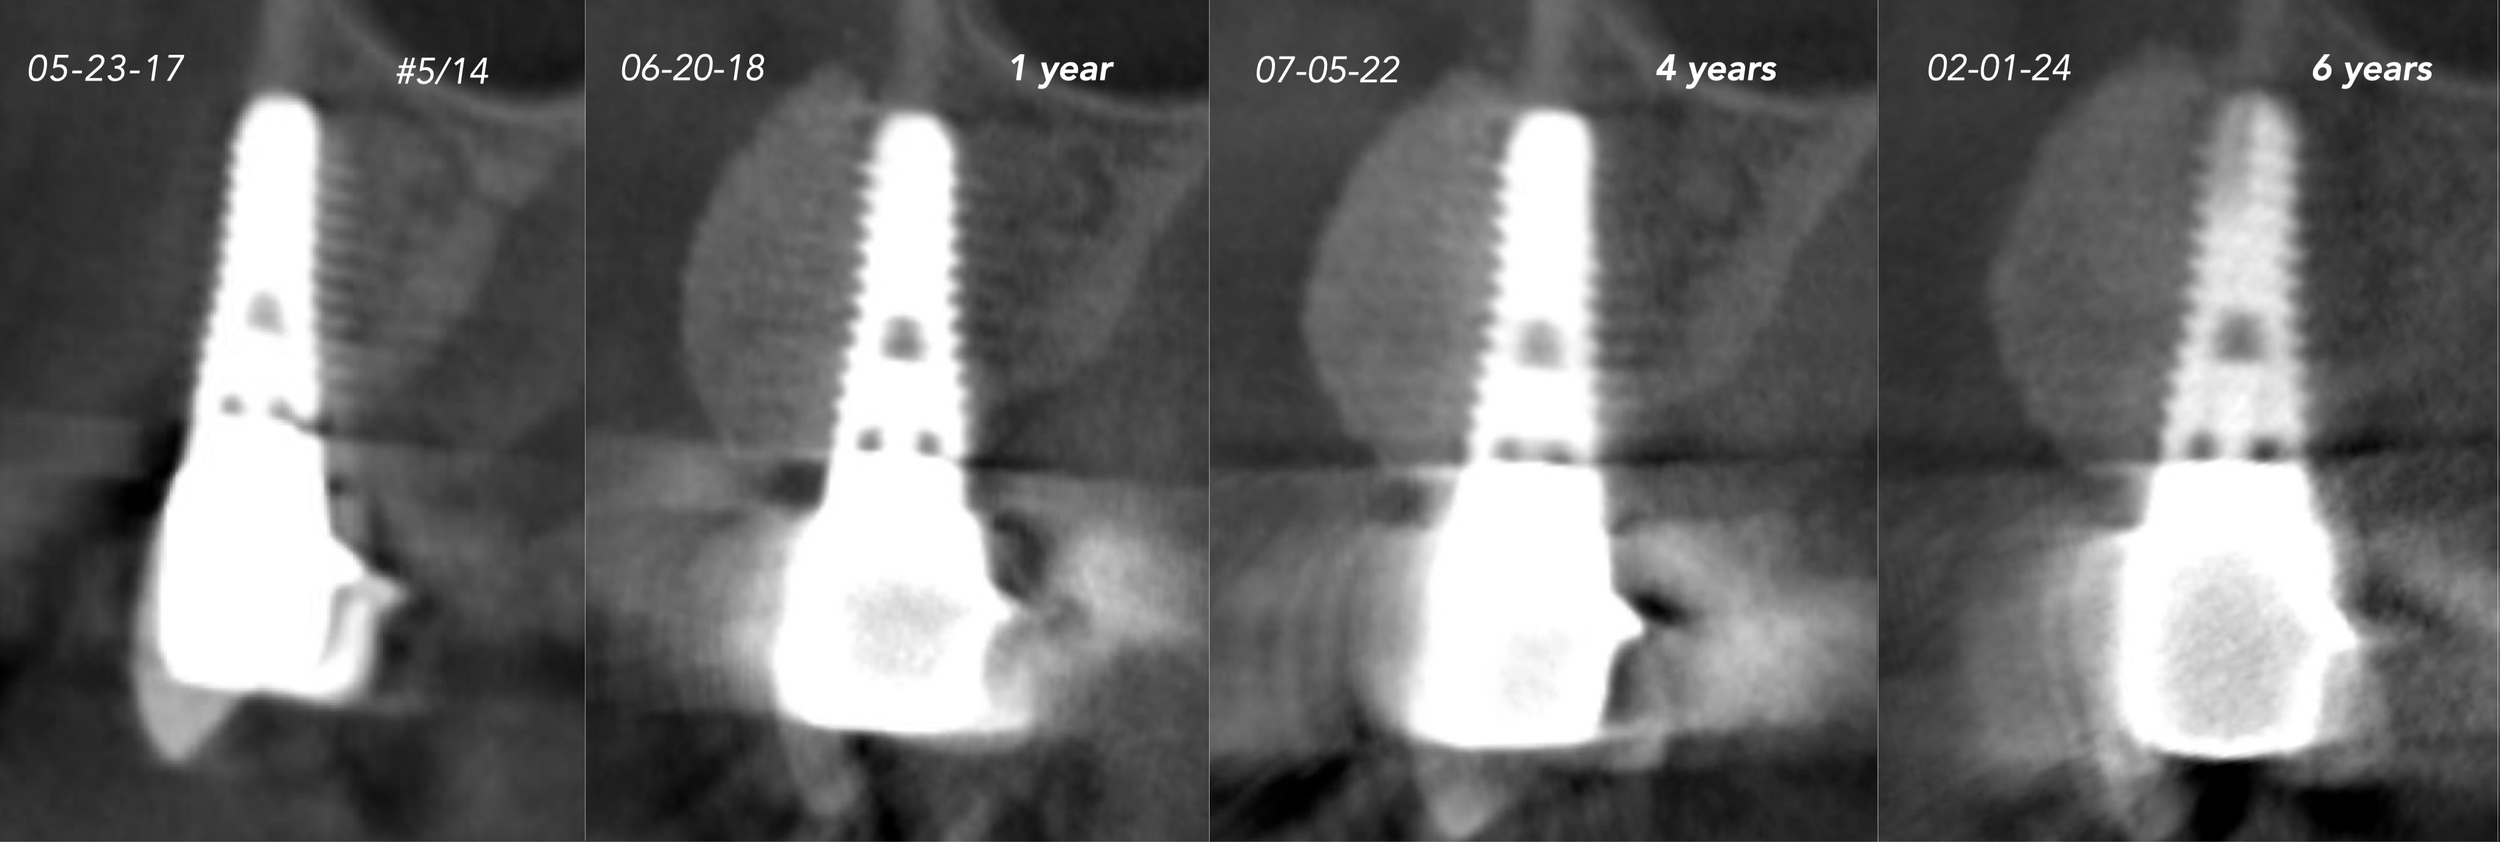

CASE 6. IMPLANT BONE DEHISCENCE